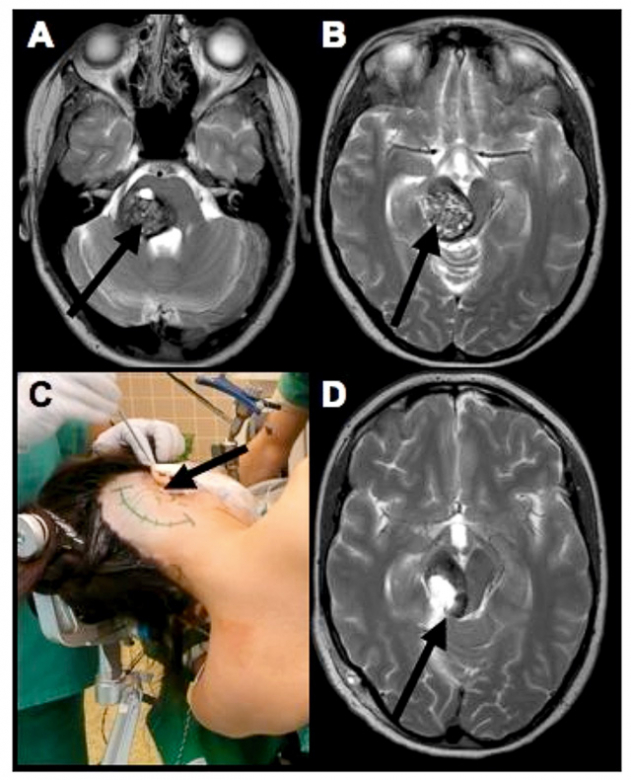

脑干海绵状血管瘤引起的脑干出血需要手术吗?海绵状血管瘤是指长在脑内的血管畸形,其中脑干部位的海绵状血管瘤是预后较差的颅内海绵状血管瘤,手...

脑干海绵状血管瘤是一种少见的脑部血管疾病,由于其位置不同,治疗难度较大。手术治疗是目前治疗脑干海绵状血管瘤的主要方式之一,但手术治疗后是...

脑干海绵状血管瘤是一种少见的脑血管疾病,发病率较低,但是由于其位置不同,手术难度大,治疗风险高,因此对于患者来说是一种危险的疾病。如果脑...

脑干海绵状血管瘤是一种严重的脑部疾病,治疗难度高、风险大,同时手术复发也是这种疾病患者经常面临的问题。手术后的恢复过程可能需要很长时间,...